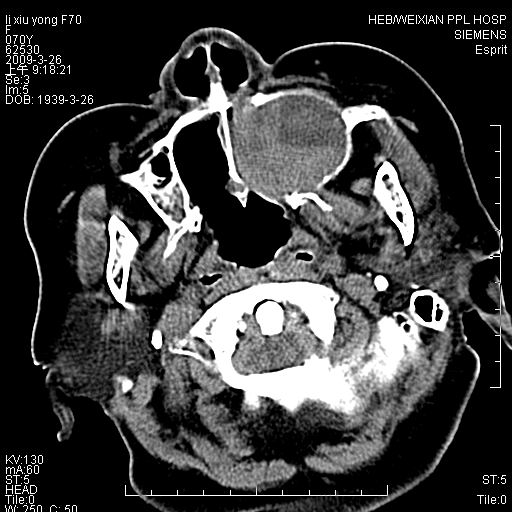

标题: CT19708:单侧上颌窦病变

老年患者,女。鼻塞多年。

考虑右侧上颌窦良性占位性病变,粘液囊肿可能性大;建议活检。

膨胀性生长,且骨质无破坏,说明时间久,良性;从密度,边缘看,内部还见坏死区,应该是实性肿瘤,定性,影像学无绝对的特异性

病灶密度很不均匀,骨壁膨胀中有断裂,考虑内翻乳头状瘤可能性大,粘液囊肿不排除

膨胀性生长,且骨质无破坏,说明时间久,良性;从密度,边缘看,内部还见坏死区,应该是实性肿瘤,定性,影像学无绝对的特异性,考虑内翻性乳头状瘤可能